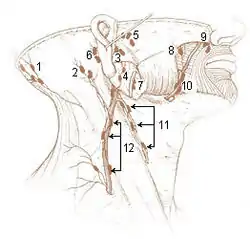

- Diagram at Baylor College of Medicine (listed as "retroauricular")